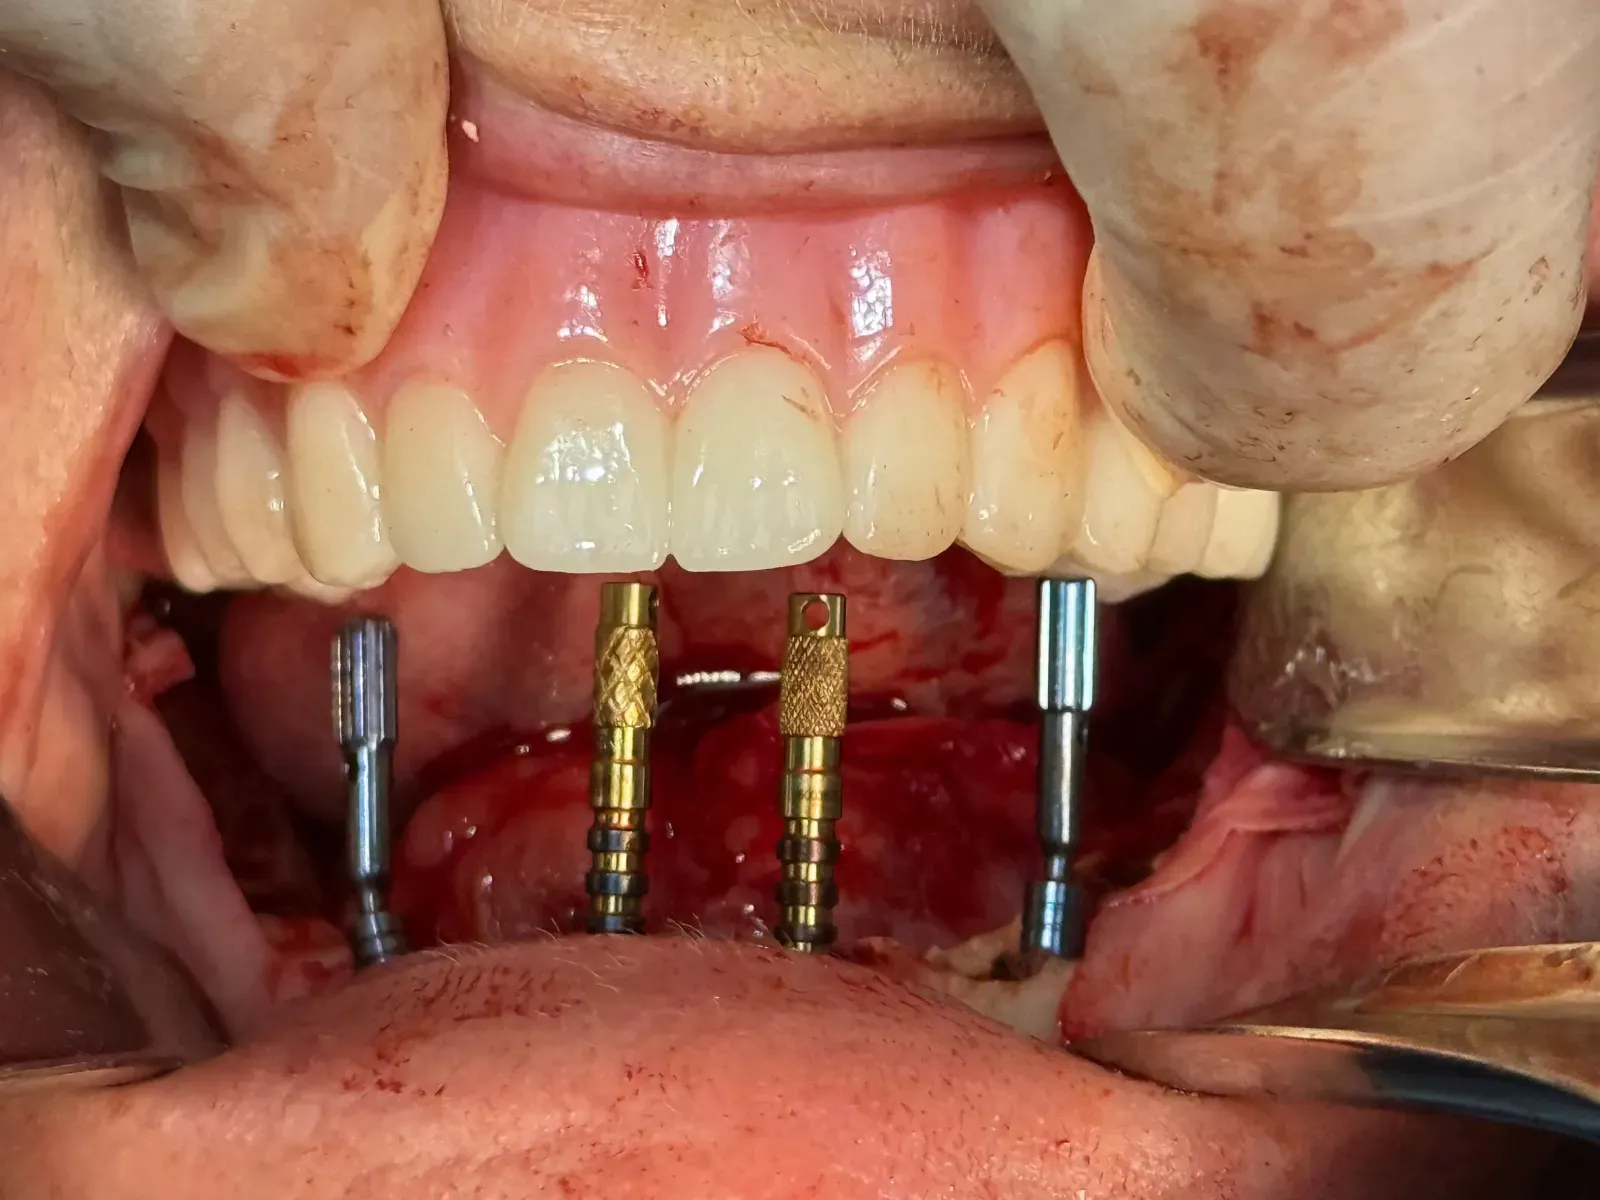

- Surgical workflows for full-arch implant placement and arch stabilization

- Immediate loading considerations and provisionalization strategies